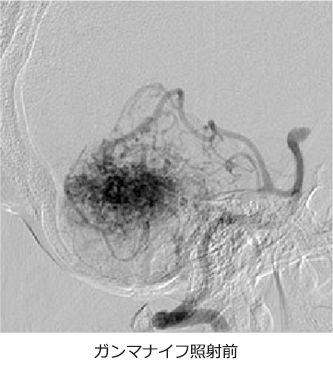

ガンマナイフやサイバーナイフと呼ばれる、特殊な放射線照射の機械でAVMに放射線を当てて、消失させる方法です。脳や血管を直接触る手術ではないので、患者さんへの負担は最も少ない方法と考えられます。摘出術に向いていない病変などに対して行われることが多い治療法です。放射線を当ててから、病変が完全に消失するまでに、2-3年程度かかると言われており、この間は出血を起こす危険性があります。また、大きな病変への治療は困難であることが多く、血管内手術で病変のサイズを縮小してから、放射線照射を行う必要がある症例もあります。

CTやMRIに加えて、脳血管撮影を施行した上で、治療方針を決定しています。出血を起こしていないものに関しては、敢えて治療をせずに、経過観察を行う場合もあります。安全に摘出可能と判断できる病変に関しては、血管内治療による塞栓術を併用して、外科的摘出術を行います。摘出術が困難ですが、治療が必要と判断される病変に関しては、塞栓術を行った後に、放射線治療を行うことをお勧めしています。 当施設には、ガンマナイフやサイバーナイフが設置されておりませんが、関連施設にご依頼させて頂き、治療前後のフォローを綿密に行っております。

治療実績

慈恵医大では、外来を受診されたAVM患者さんのうちの約6割の患者さんが、何らかの治療を受けられています。このうちの半数の患者さんが、血管内治療を行った後に、放射線外科治療を施行されています。この結果、照射後3年以上経過した患者さんの約8割で病変の完全消失が確認されています。